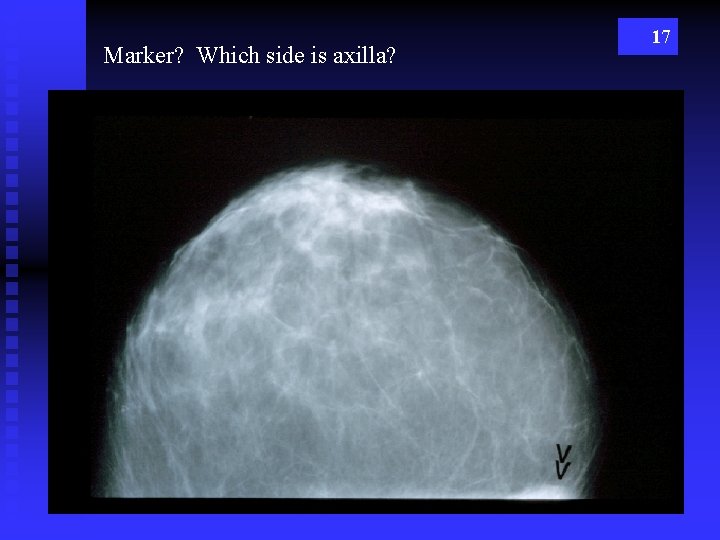

Marker? Which side is axilla? 17